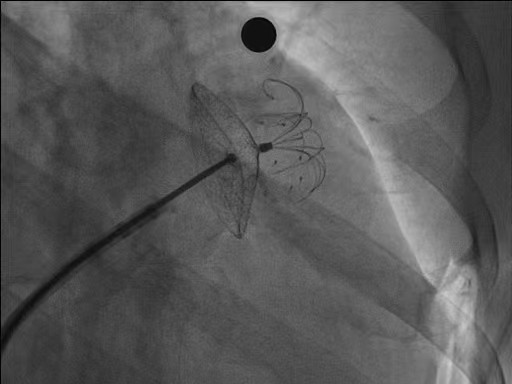

它通过穿刺股静脉送导管经右心房→左心房→左心耳,最后左心房和左心耳交界处用一个盘状封堵器塞住,封闭左心耳的血栓,这样就起到了预防脑中风作用。

经皮左心耳封堵术效果肯定,又不需要长期服用抗凝药引起严重出血的风险,手术时间大概在 40~60 分钟左右。